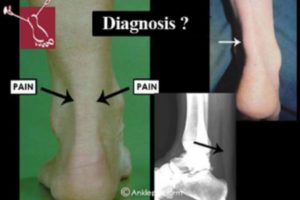

It has been customary practice for medical terms to be named after a person—familiar eponymous terms serve as shorthand during communication with colleagues. Specifically, as it relates to tendon–related disorders, several of these disorders can be distinguished and for each pathology different definitions and...

By Kim T. M. Opdam, Ruben Zwiers, Johannes I. Wiegerinck, C. Niek van Dijk, and Ankle Platform Study Collaborative – Science of Variation Group